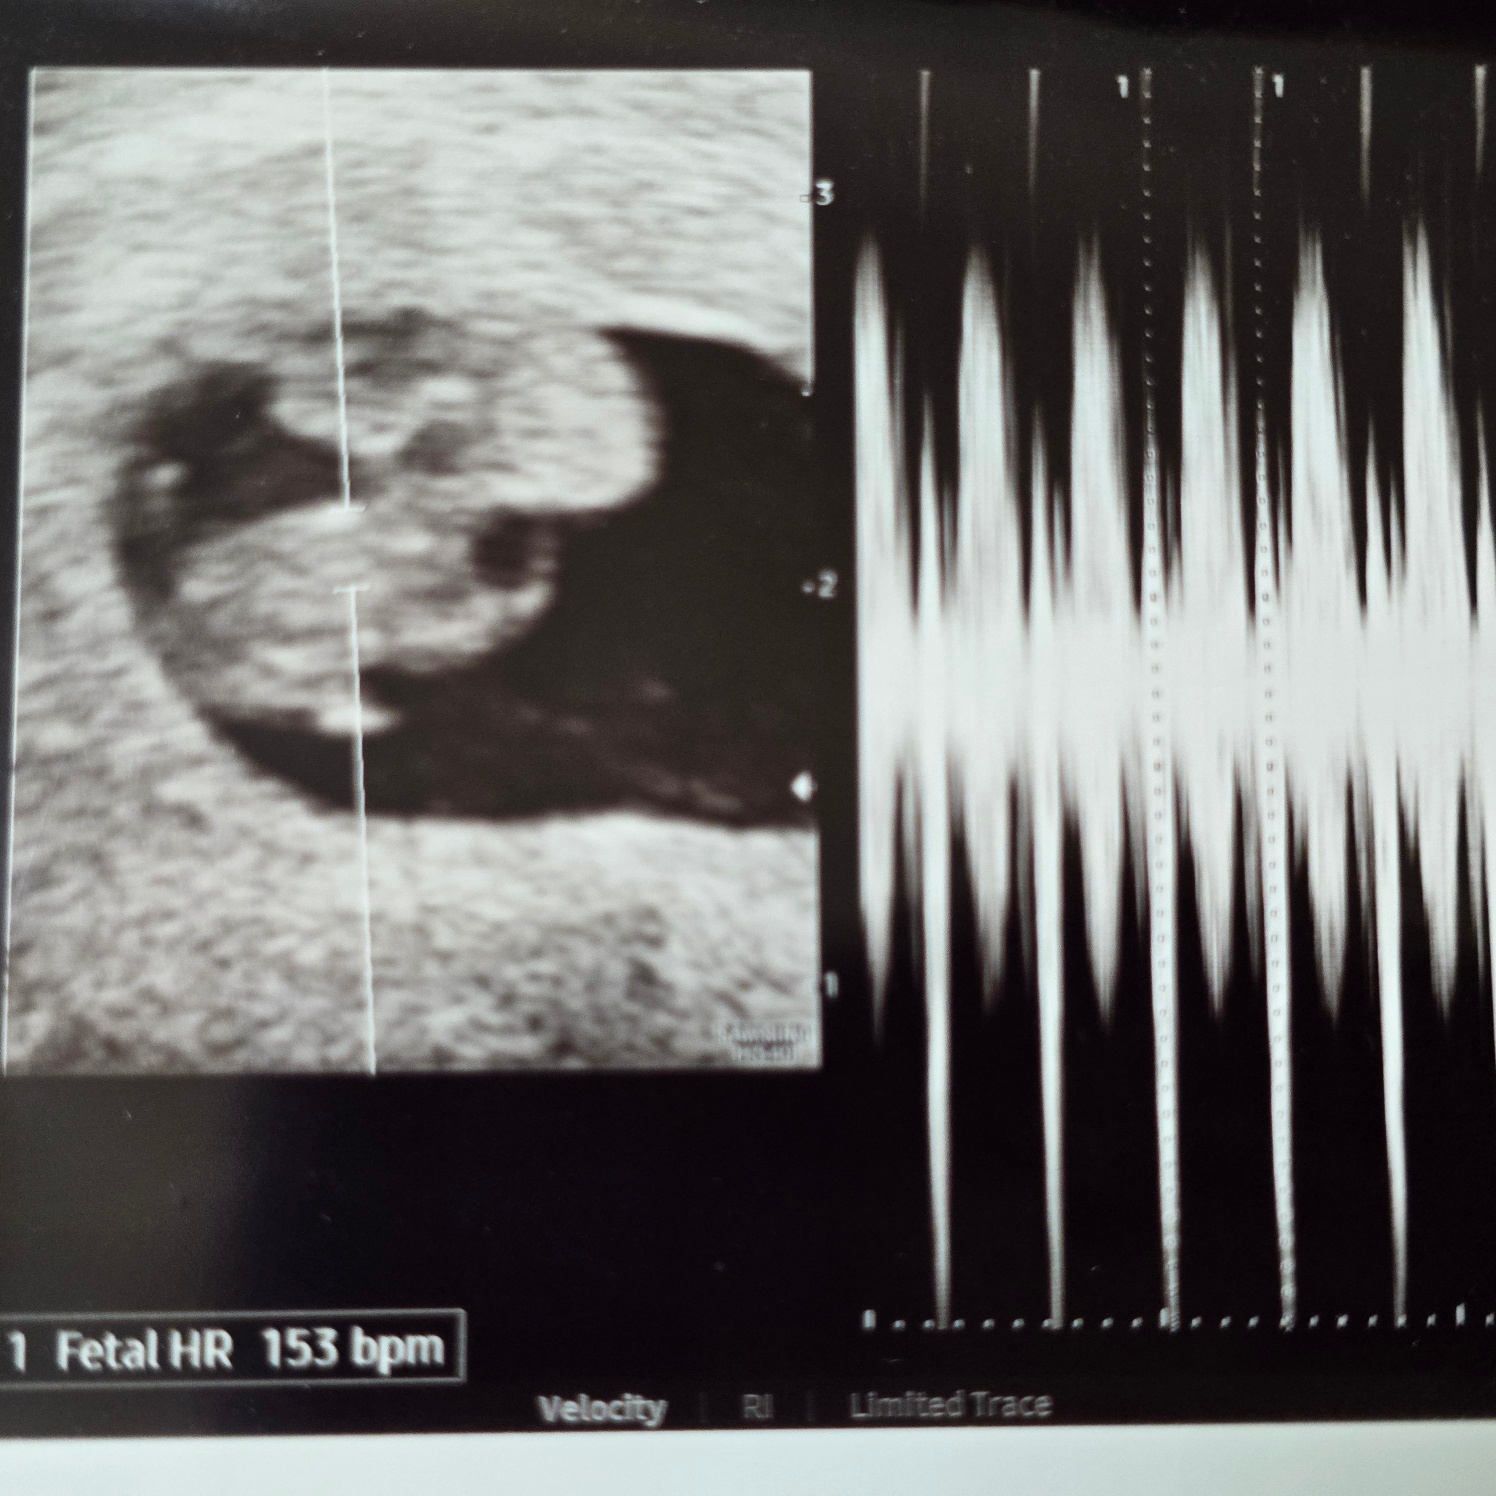

그리고 아기 심장소리까지 들었다!!!!

크기는 4일 작지만 따라가기도 하고 착상이 조금 늦었다 생각하면 이대로 유지만 해도 괜찮을 거라고 말씀해 주셨다!!